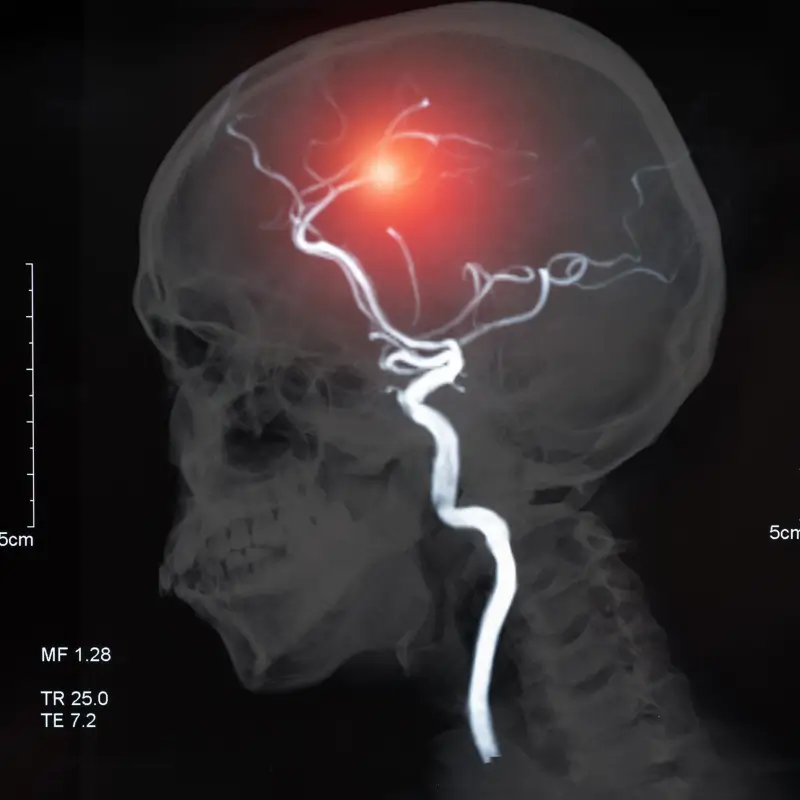

A hemorrhagic stroke Stroke caused by bleeding inside or around the brain.

- Aneurysm: A ballooning of a weakened portion of a blood vessel can burst, leading to hemorrhage.

- Subarachnoid Hemorrhage: This type occurs when there is bleeding between the brain and the thin tissues that cover it (subarachnoid space), often due to a ruptured aneurysm.

- CT Scan: A computed tomography scan is usually the first test performed to detect bleeding in the brain.

- MRI: Magnetic resonance imaging can provide more detailed images of the brain and help identify the exact location and extent of bleeding.

- Cerebral Angiography: This test involves injecting dye into the blood vessels to detect abnormalities, such as aneurysms or AVMs.